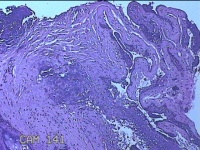

性别

男

年龄

44岁

临床诊断

皮脂腺囊肿

一般病史

右面部起疹12月,不痒。

标本名称

面部肿物

大体所见

灰白粉红色肿物0.5x0.3x0.2cm一个,表面糜烂。